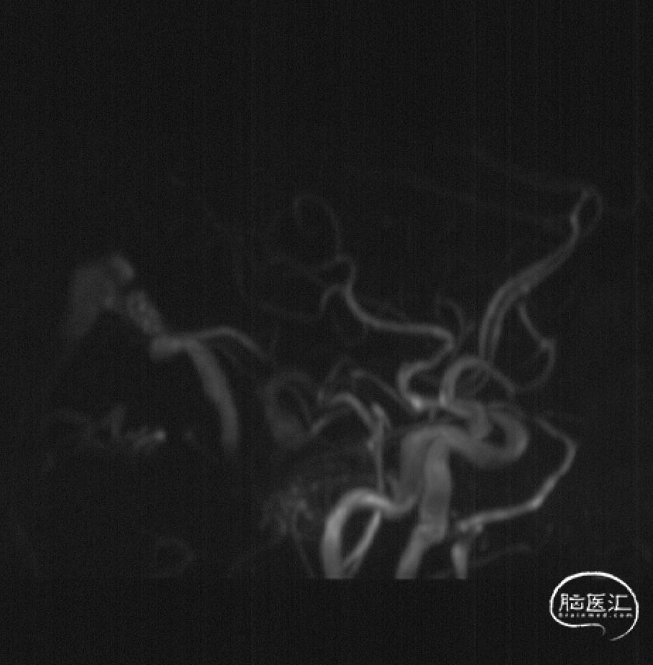

术前MRA

MRA见后颅窝早显的异常扩张的静脉